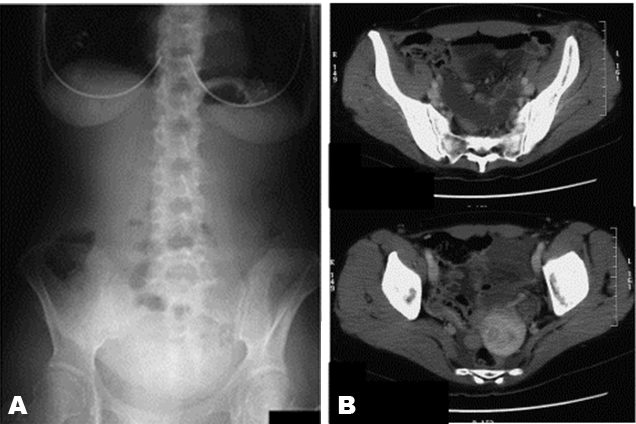

A 49-year-old woman presented with intermittent abdominal pain around her umbilicus and nausea. There was no rebound tenderness and abdominal guarding. She had the symptoms for a half day before coming to our hospital. She had myoma of the uterus and cavernous hemangioma but had never undergone surgery. Laboratory findings showed only slight leukocytosis, and X-ray showed a few dilated small bowel loops in the abdomen. We found the same distended small bowel loops in the CT scan (Figure 1).

Figure 1: (A, B) The X-ray and computed tomography (CT) scan were taken on admission. The X-ray showing no abnormal gas. Axial CT scan of the abdomen with intravenous contrast administration showing only distended small intestine.